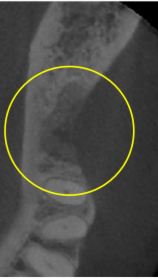

抜歯のう胞摘出

Perio Wave+Er:YAGレーザー+コールドレーザーで治療した箇所の経過です。

左から直後、1ヶ月経過時、2ヶ月経過時の画像です。